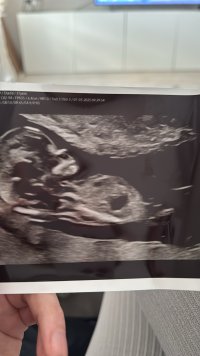

Nub-teorian mukaan sukupuolen voi määrittää jo nt-ultrassa genitaalikyhmyn asennon perusteella. Voit lukea aiheesta lisää täältä.

Kiinnostaako teitä sukupuolen määrittäminen kyseisen teorian avulla? Katsotteko ultrakuvia sillä silmällä?